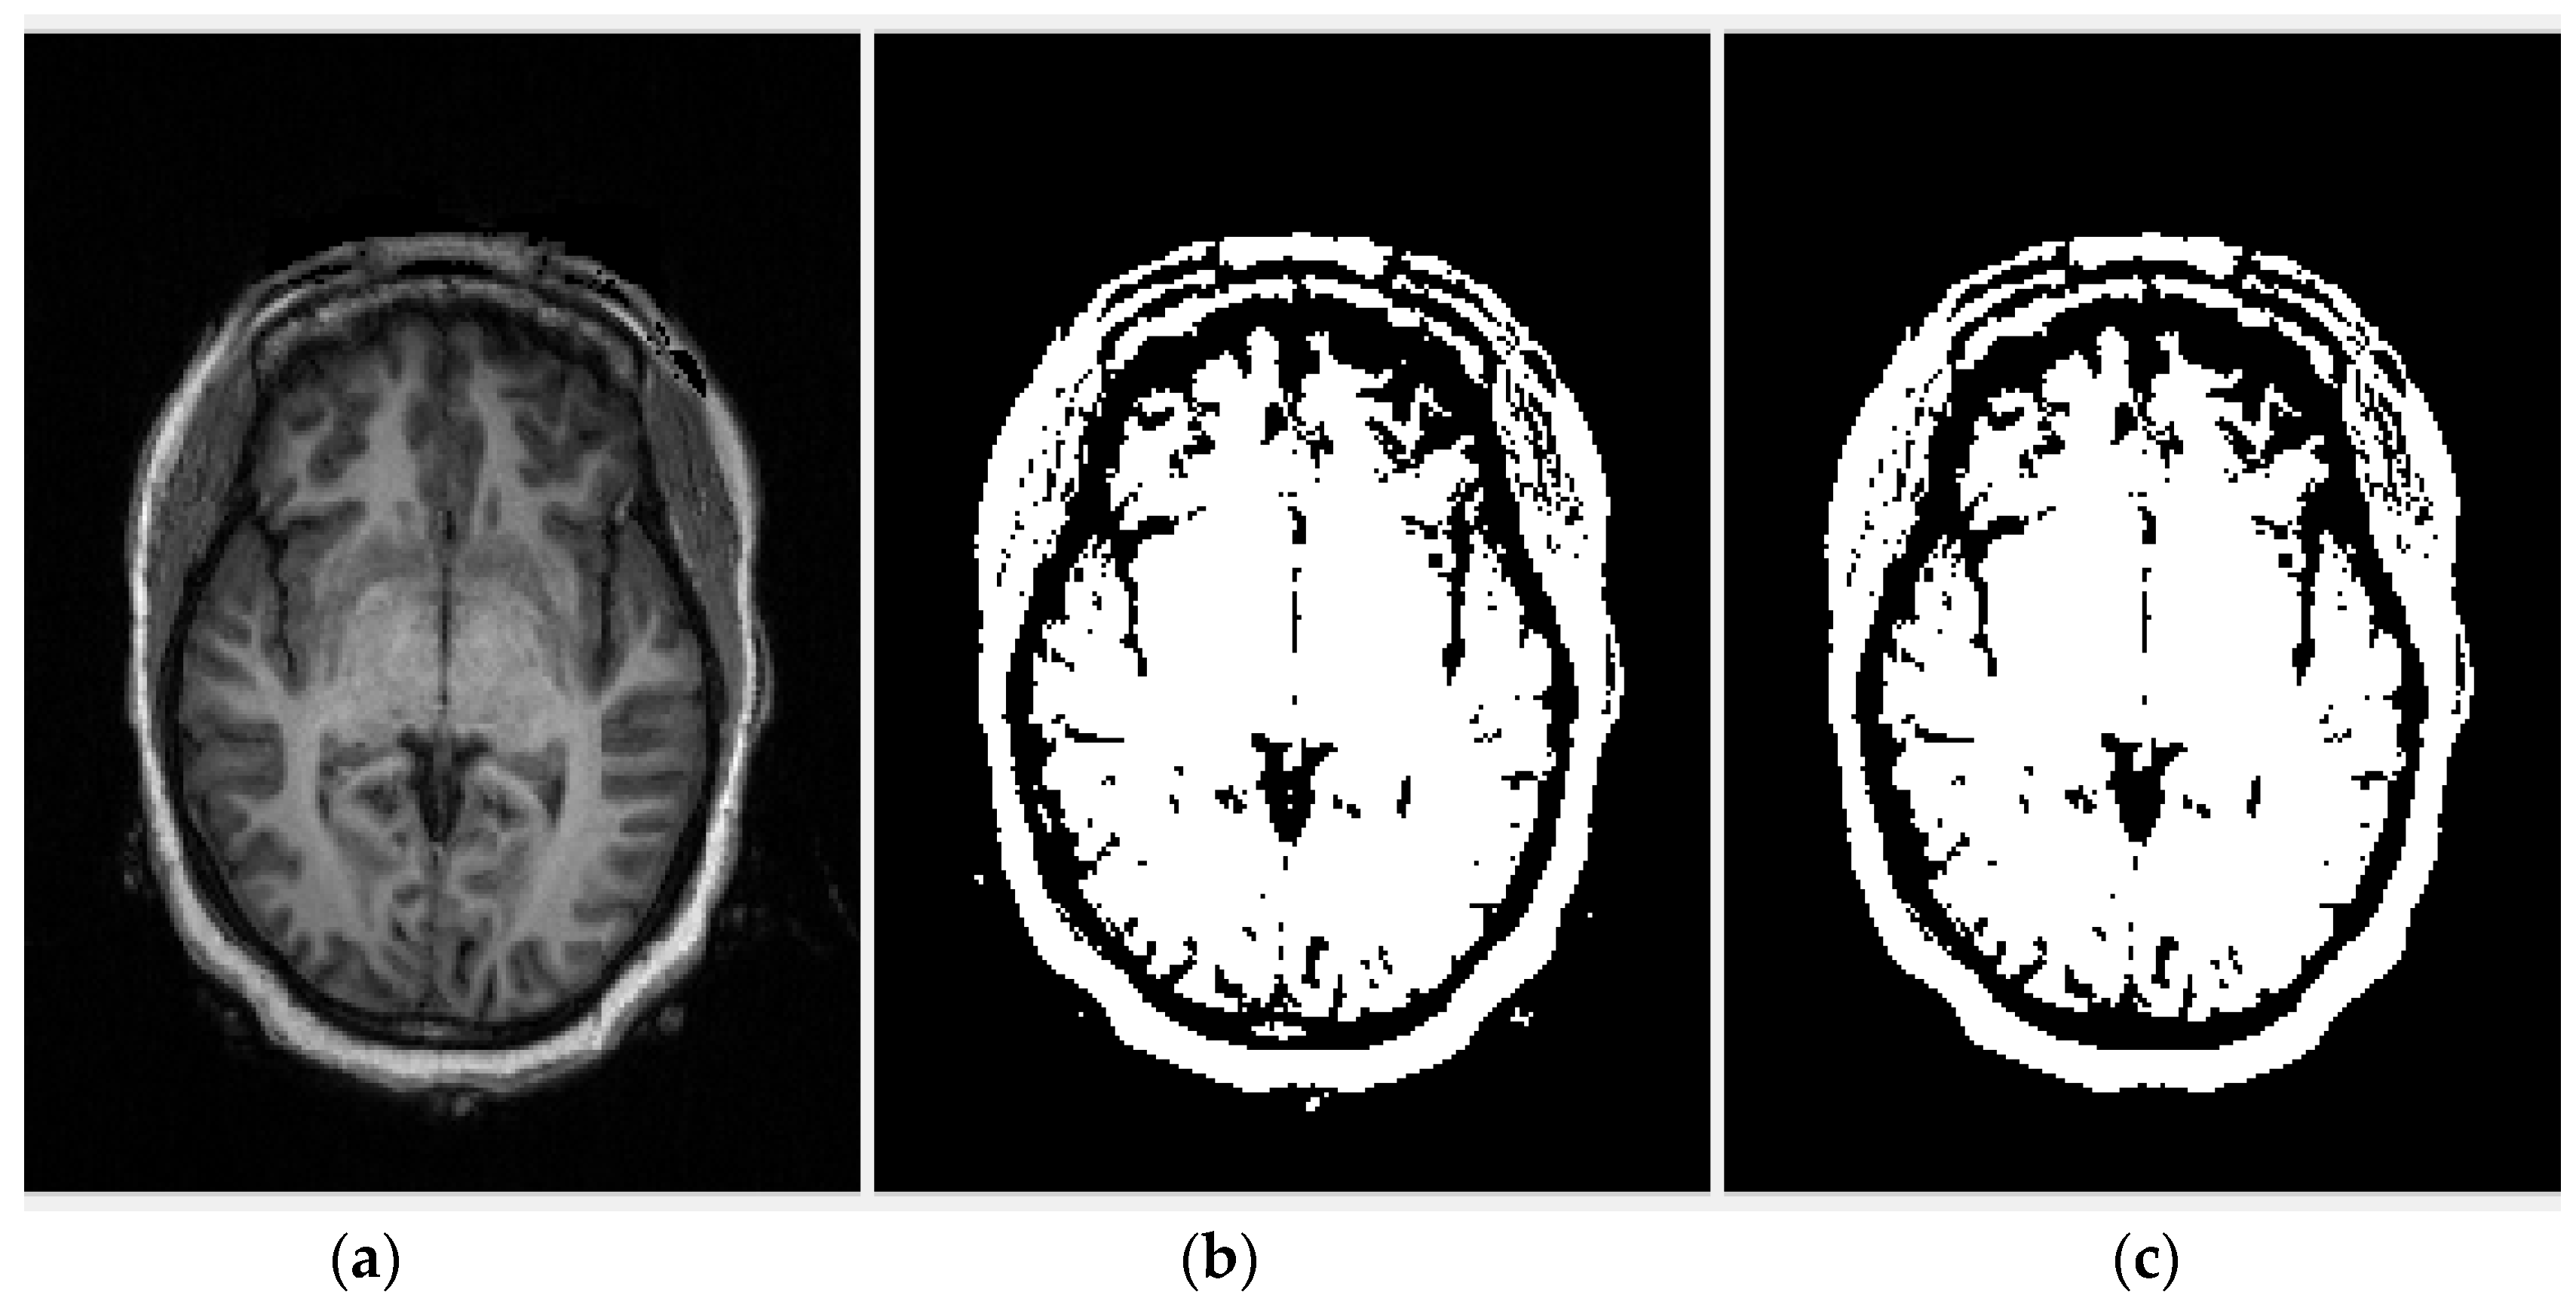

2.2.1. Region of Interest Extraction